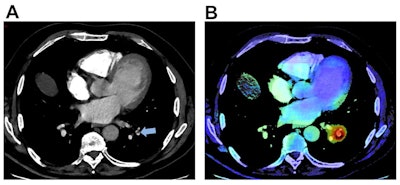

The researchers retrospectively applied a PE detection algorithm from Aidoc to 1,202 patients with suspected PE from September to December 2019. Of these patients, 190 (15.8%) had true PE. They then compared the AI results with the gold standard, which was determined via a retrospective review of the CTPA exam, radiological and clinical reports, AI outputs, and patient outcomes.

The algorithm identified 19 PEs that were missed by the radiologists -- a rate of approximately one misdiagnosed PE for every 63 CTPA scans. Although AI produced higher sensitivity and negative predictive value than the emergency radiologists in the study, those differences did not reach statistical significance. The higher specificity, positive predictive value, and accuracy for the radiologists was statistically significant, though.